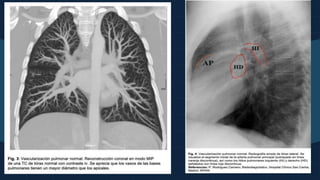

PATRÓN VASCULAR NORMAL

La vasculatura pulmonar

sigue una distribución

arbiriforme.

Se debe ver del pulmón 1-

2 cm por dentro de la

pleura

Ambos hilios deben ser

simetricos (el derecho más

caudal)

10cm

Se identifica un crecimiento de ambos

hilios pulmonares, generalmente de

manera simétrica, a expensas de las

arterias pulmonares derecha e

izquierda y de la arteria pulmonar

principal. Habitualmente acompañado

de disminución de calibre de los vasos

pulmonares periféricos.

PATRÓN DE HIPERTENSIÓN ARTERIAL

PULMONAR

Una medida a recordar para identificar el

crecimiento de las arterias pulmonares en la

radiografía simple PA es el diámetro de la

arteria interlobar: por encima de 16-17 mm se

considera que está dilatada